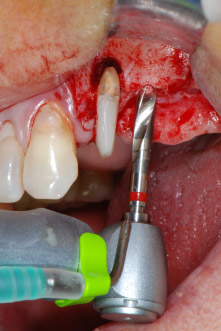

Implant beds were prepared at sites 25 and 26 with rotary instruments, used in a contra-angle handpiece with a 20 : 1 transmission ratio with an updated powerful implant motor (Implantmed, W&H) (Fig. 8).

The implant bed was prepared with a new implant motor (Fig. 20), in combination with a contra-angle handpiece specifically designed for oral surgery and implantology.

The transmission rate of 20:1 together with the implant motor’s high torque of up to 6.2 Ncm allowed for slow speed preparation, implant insertion and thread cutting. Final preparation up to the sinus membrane was again performed with the piezoelectric unit and a round diamond instrument.